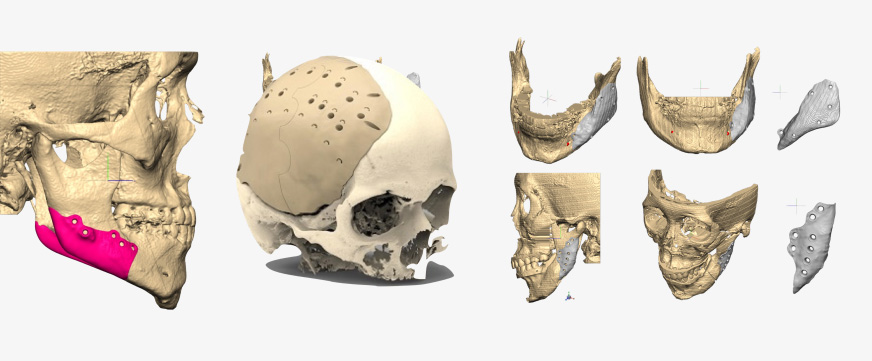

Jaw segmentation

- Skull data can be freely osteotomized according to technique preferred by oral surgeon

- Osteotomy position, range, & amount can all be adjusted depending on patient characteristics

- Combining osteotomy segments verifies anatomical changes during bone deletion & bone movement for feasible & precise surgical plan

Saw Guides

- Customized for each patient to ensure precise bone incisions & deletions

FACEGIDE Plates

- Customized for each patient

- Reduced surgery time as no need to bend or cut customized plates